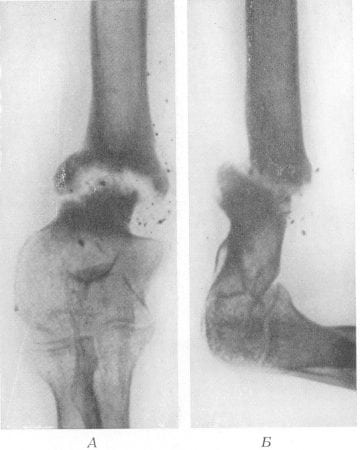

Если выразиться проще, псевдоартроз – это патологический сустав, возникший в том месте, где его быть не должно. К примеру, он может сформироваться в теле большеберцовой кости и привести к аномальной подвижности ее фрагментов. На рентгенограммах можно увидеть четкую щель между отломками и полное закрытие костномозговых каналов замыкательными пластинками.

Поначалу ложный сустав имеет мало общего с истинным. Однако со временем замыкательные пластины покрываются хрящевой тканью, превращаясь в типичные суставные поверхности. Вокруг дефекта разрастается фиброзная ткань, которая в итоге образует что-то вроде суставной капсулы. Псевдоартроз становится все больше похожим на настоящий сустав.

Поставить диагноз «псевдоартроз» врачи могут не ранее, чем через 6-8 месяцев после перелома. Для этого им достаточно проанализировать результаты рентгенологического исследования.